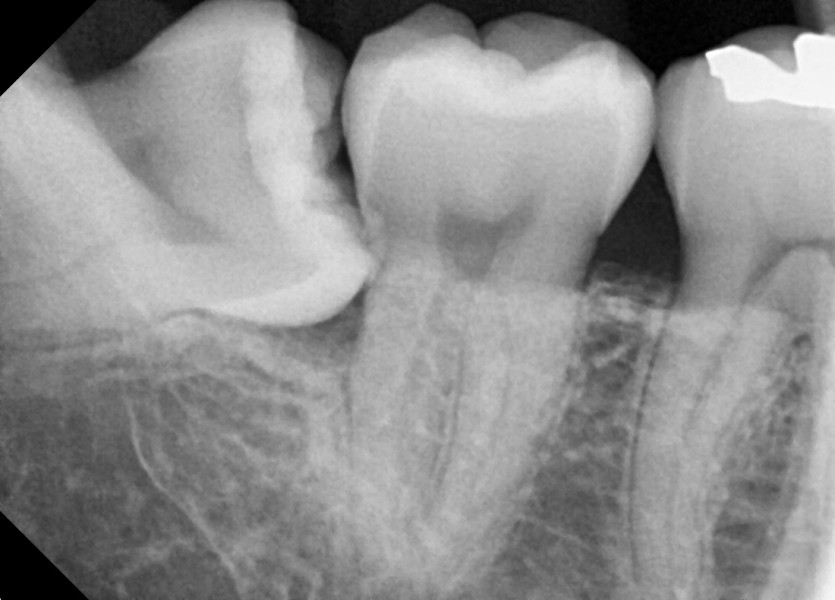

#48 사랑니 발치

구강 외과 전문의가 당일 발치했습니다.